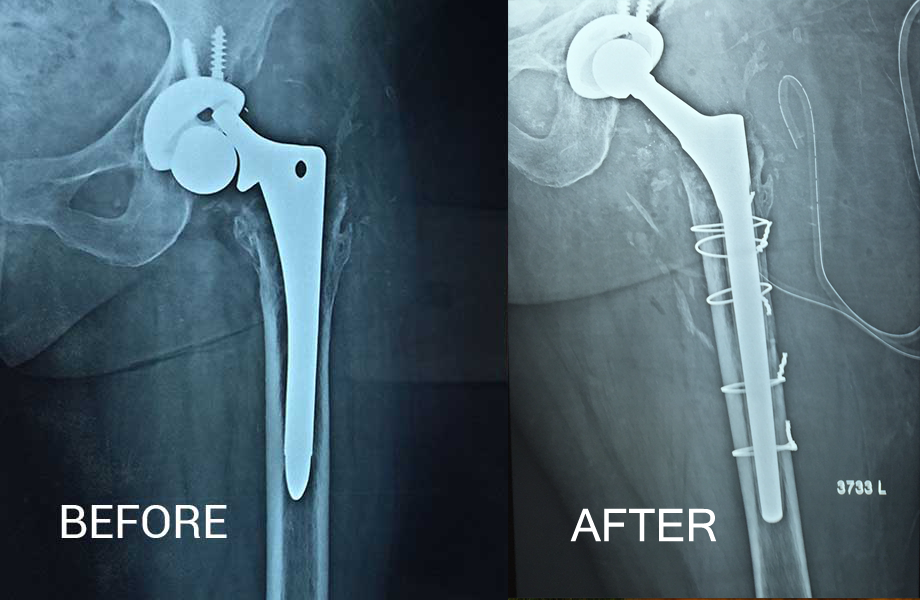

Revision Hip Replacement